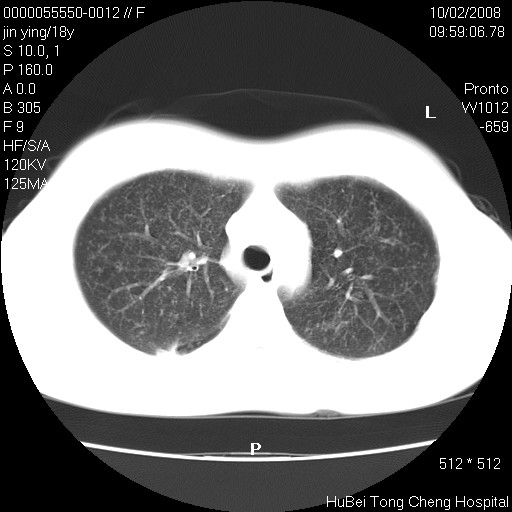

患者 女,18y。发热十余天,伴咳嗽。pe:t39⒈℃,bp 110/80mmhg,p 86次/min。神清,精神欠佳。双肺可闻及少许湿罗音。既往史不详。

临床诊断:肺部感染?

胸部ct轴位平扫(层厚10mm,螺距1.5,重建间隔10mm),图像如下: